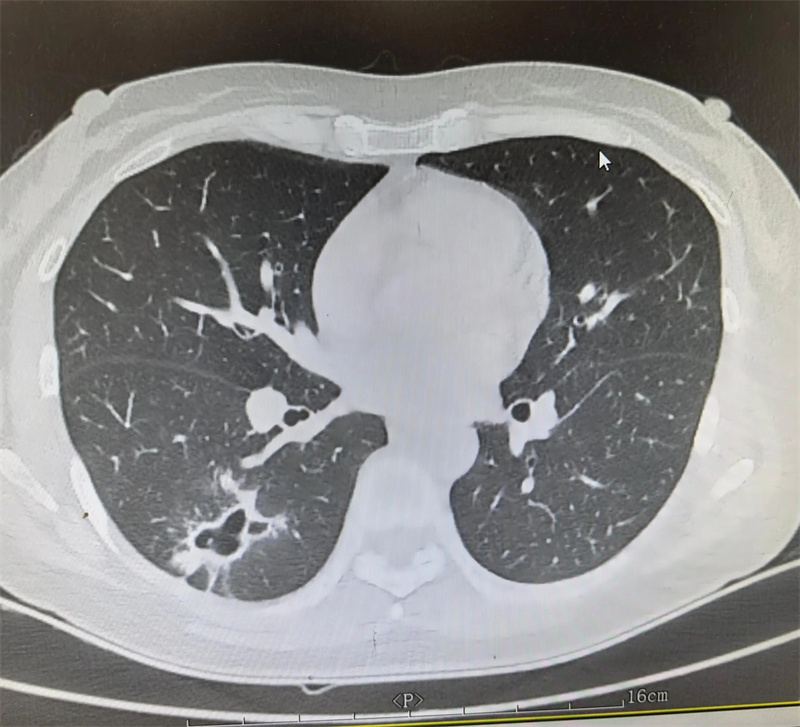

胸外科(二疗区)主任田子刚受邀参与,结合艾利影像学检查、肺功能评估及全身基础状况,与孙集思主任团队反复研讨手术指征、手术方式及围手术期风险防控要点。经过充分论证,最终确定实施“右肺下叶切除手术”。

手术当日,田子刚主任主刀,与团队成员密切配合,凭借精湛的技术,精准操作、精细剥离,完整切除病变肺组织,同时最大限度保留健康肺功能,手术过程十分顺利。